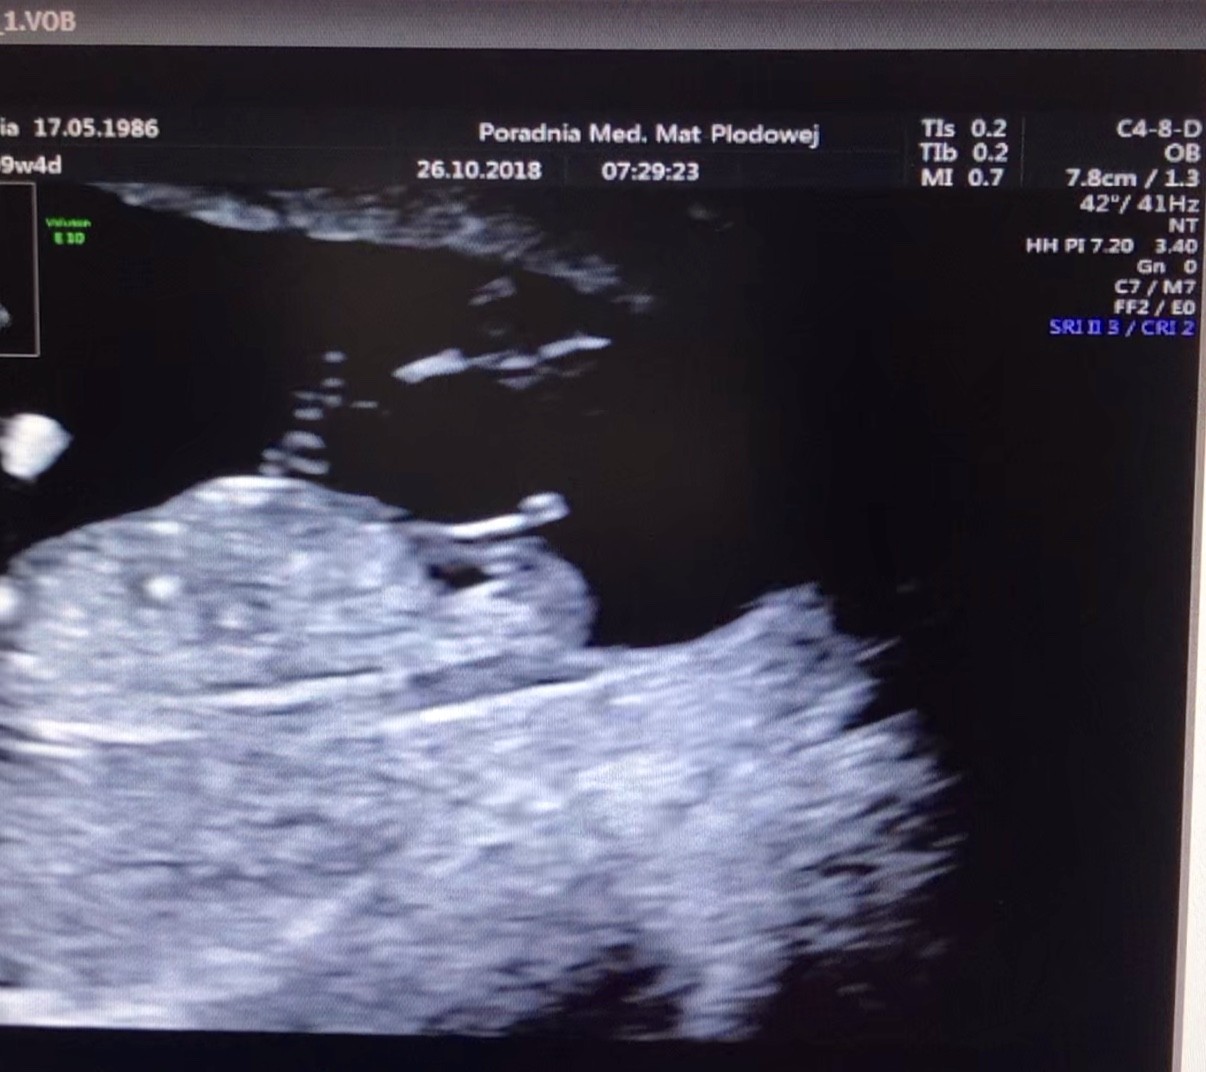

Usg chłopak czy dziewczynka

Witam w 19 tygodniu ciąży dowiedziałam się ze będę miała dziewczynkę w 20 tyg okazało się jednak , że to chłopak. Sama już nie wiem bo na jednym usg widać na pewno dziewuche a na drugim chłopca. Może to pempowina ?? Może ktoś mi pomoże rozwiązać ta zagadkę

Bardzo dziękuję za wyjaśnienie bo zupełnie nie mialam.o tym pojęcia najważniejsze jest zdrowie dziecka. Ale cały czas podświadomie czuję dziewczynkę. Gdy lekarz w sumie bez przekonania bo dziecko za bardzo się wierciło powiedział chłopak nie mogłam uwierzyć. Później dwa razy było że dziewczynka i jestem zupełnie zagubiona. A na tym moim USG ten siusiak wydaje się mi zwyczajnie za duży. Przy pierwszym.Synku